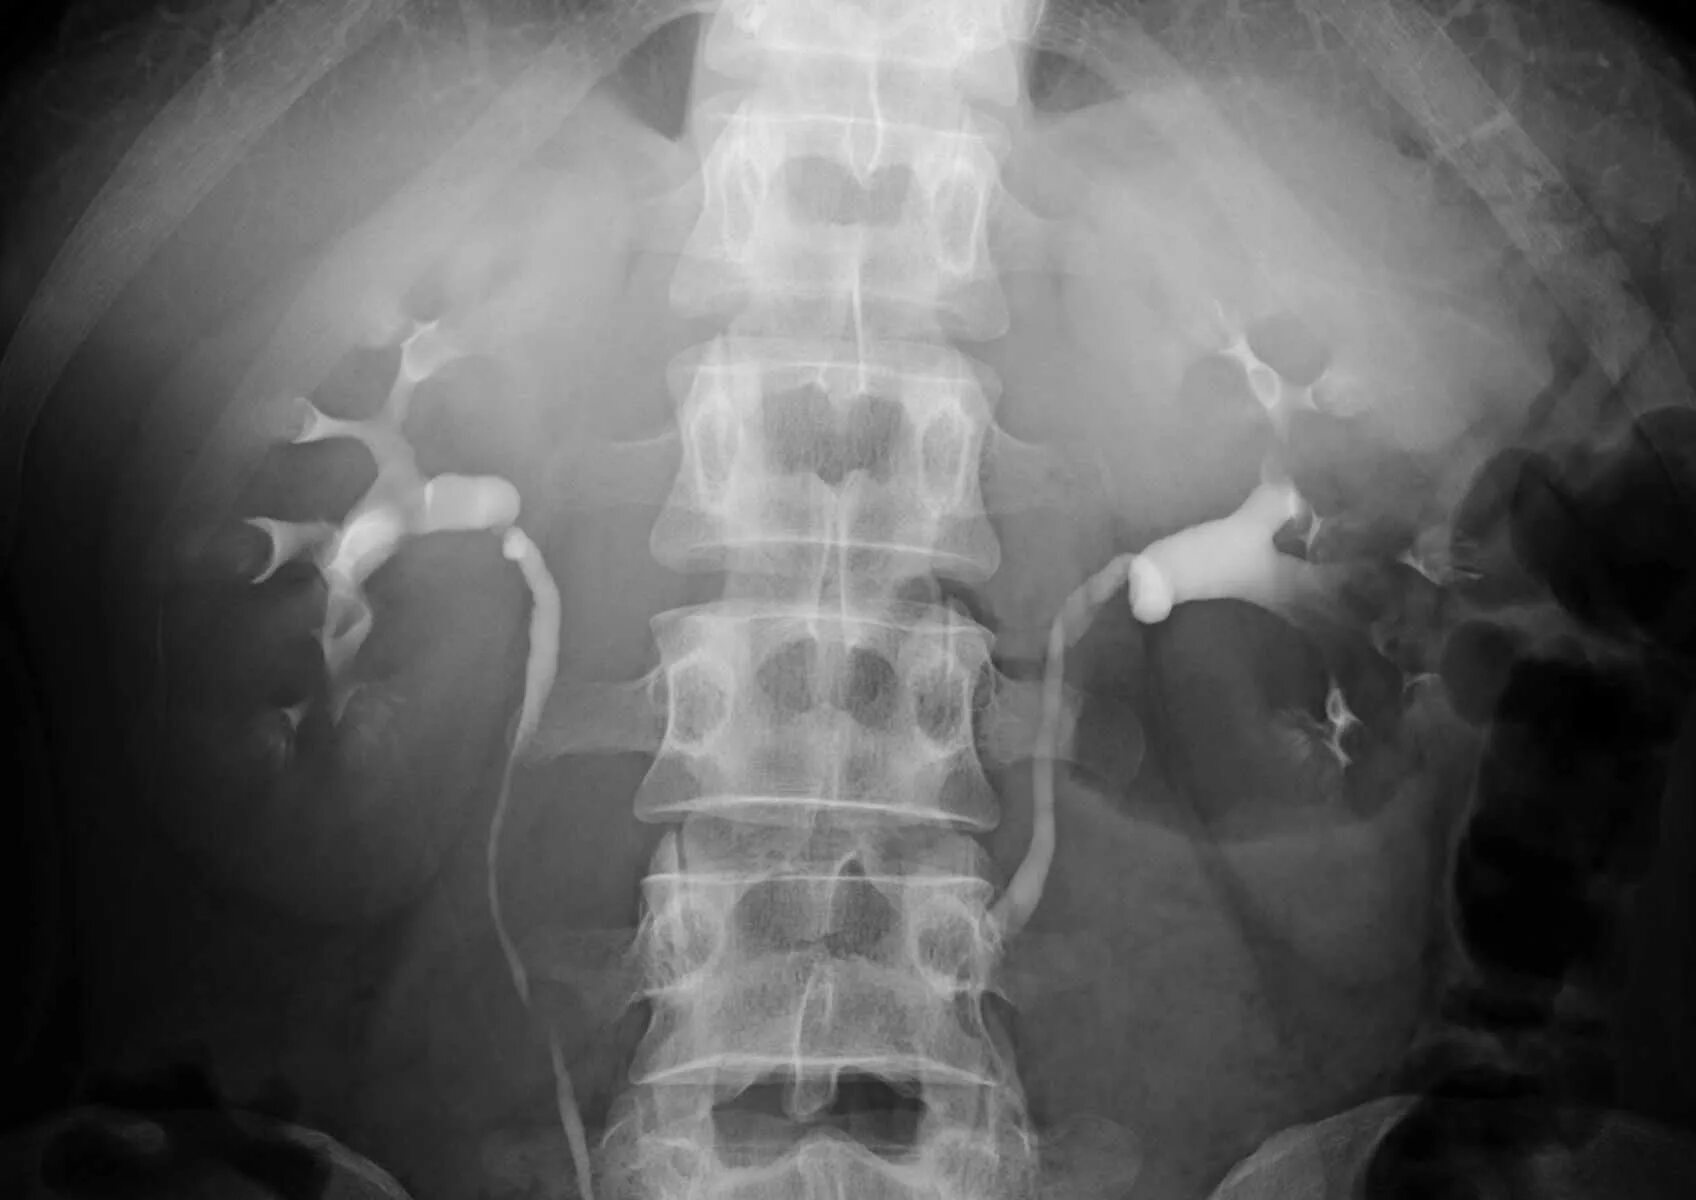

Урография с контрастом